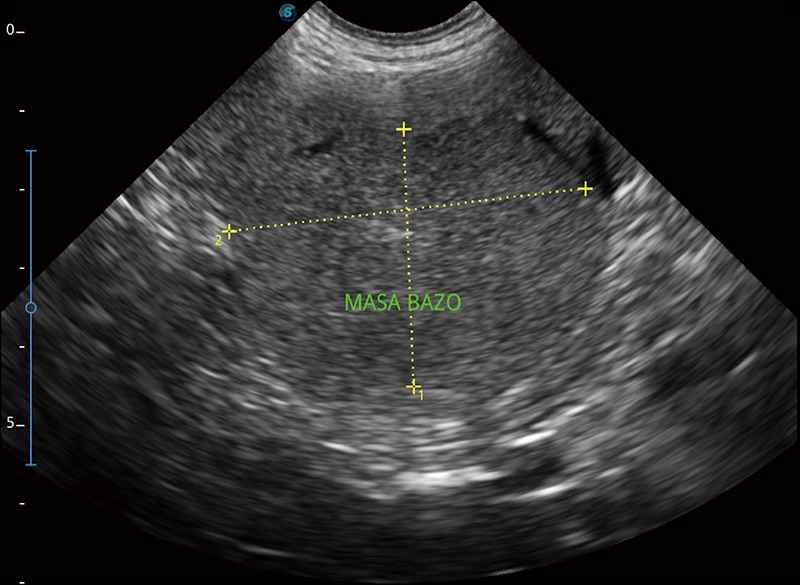

α1卓越的图像质量和便捷的工作流程,使每位宠物医生都能轻松扫查。其全面的兽用应用功能和紧凑型的结构设计,可以满足动物检查的多种需要。专业的预设检查模式和多领域测量软件包有助于为不同类型的动物提供检查, 让宠物医生能够出色的完成工作。

扩展成像

支持线阵和凸阵探头,一键操作即可获得更宽的图像视野